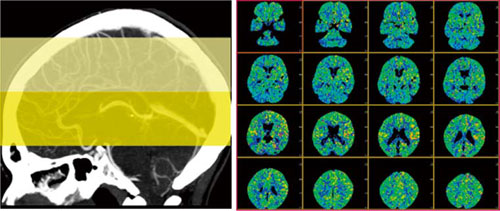

フィリップスでは,CT perfusion解析ソフト「Advanced Brain Perfusion」を本体コンソール,自社製ワークステーション「Extend Brilliance Workspace」およびthin clientサーバ「Brilliance Workspace Portal」に搭載が可能である(図1)。

図1 Perfusion Maps |